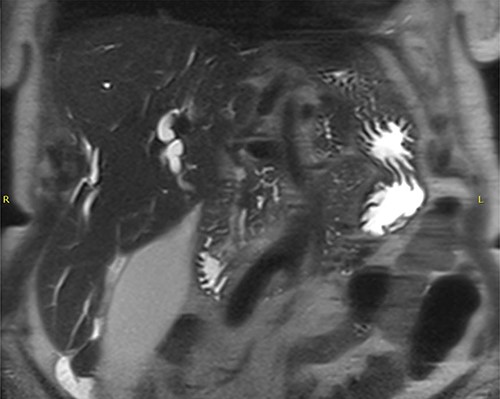

Liver function tests (LFTs) showed a greatly elevated bilirubin of 289 umol/L, with globally elevated alanine aminotransferase (ALT) 179 U/L, alkaline phosphatase (ALP) 400 U/L and gamma-glutamyl transferase (GGT) 593 U/L. IgG4 was 7.97 g/L, which is seven times normal (reference range 0.04–0.86 g/L). The tumour marker Ca19.9 was significantly elevated at 3295 kU/L (normal <34 kU/L). A magnetic resonance cholangiopancreatography (MRCP) revealed a soft tissue mass at the head of the pancreas, amputating the biliary tree and highly suspicious for cholangiocarcinoma (Fig. 2). With markedly elevated Ca 19–9 and IgG4 titres, combined with imaging results suspicious for cholangiocarcinoma, we were presented with a diagnostic dilemma: was the mass an inflammatory pseudotumour associated IgG4-RD, a malignancy or both?

MRCP + pancreas—dilated intrahepatic biliary ducts and common bile duct with abrupt cut-off due to presence of a soft tissue mass highly suspicious for a cholangiocarcinoma; multifocal areas of heterogeneous signal and restricted diffusion in both kidneys may relate to IgG4 disease.